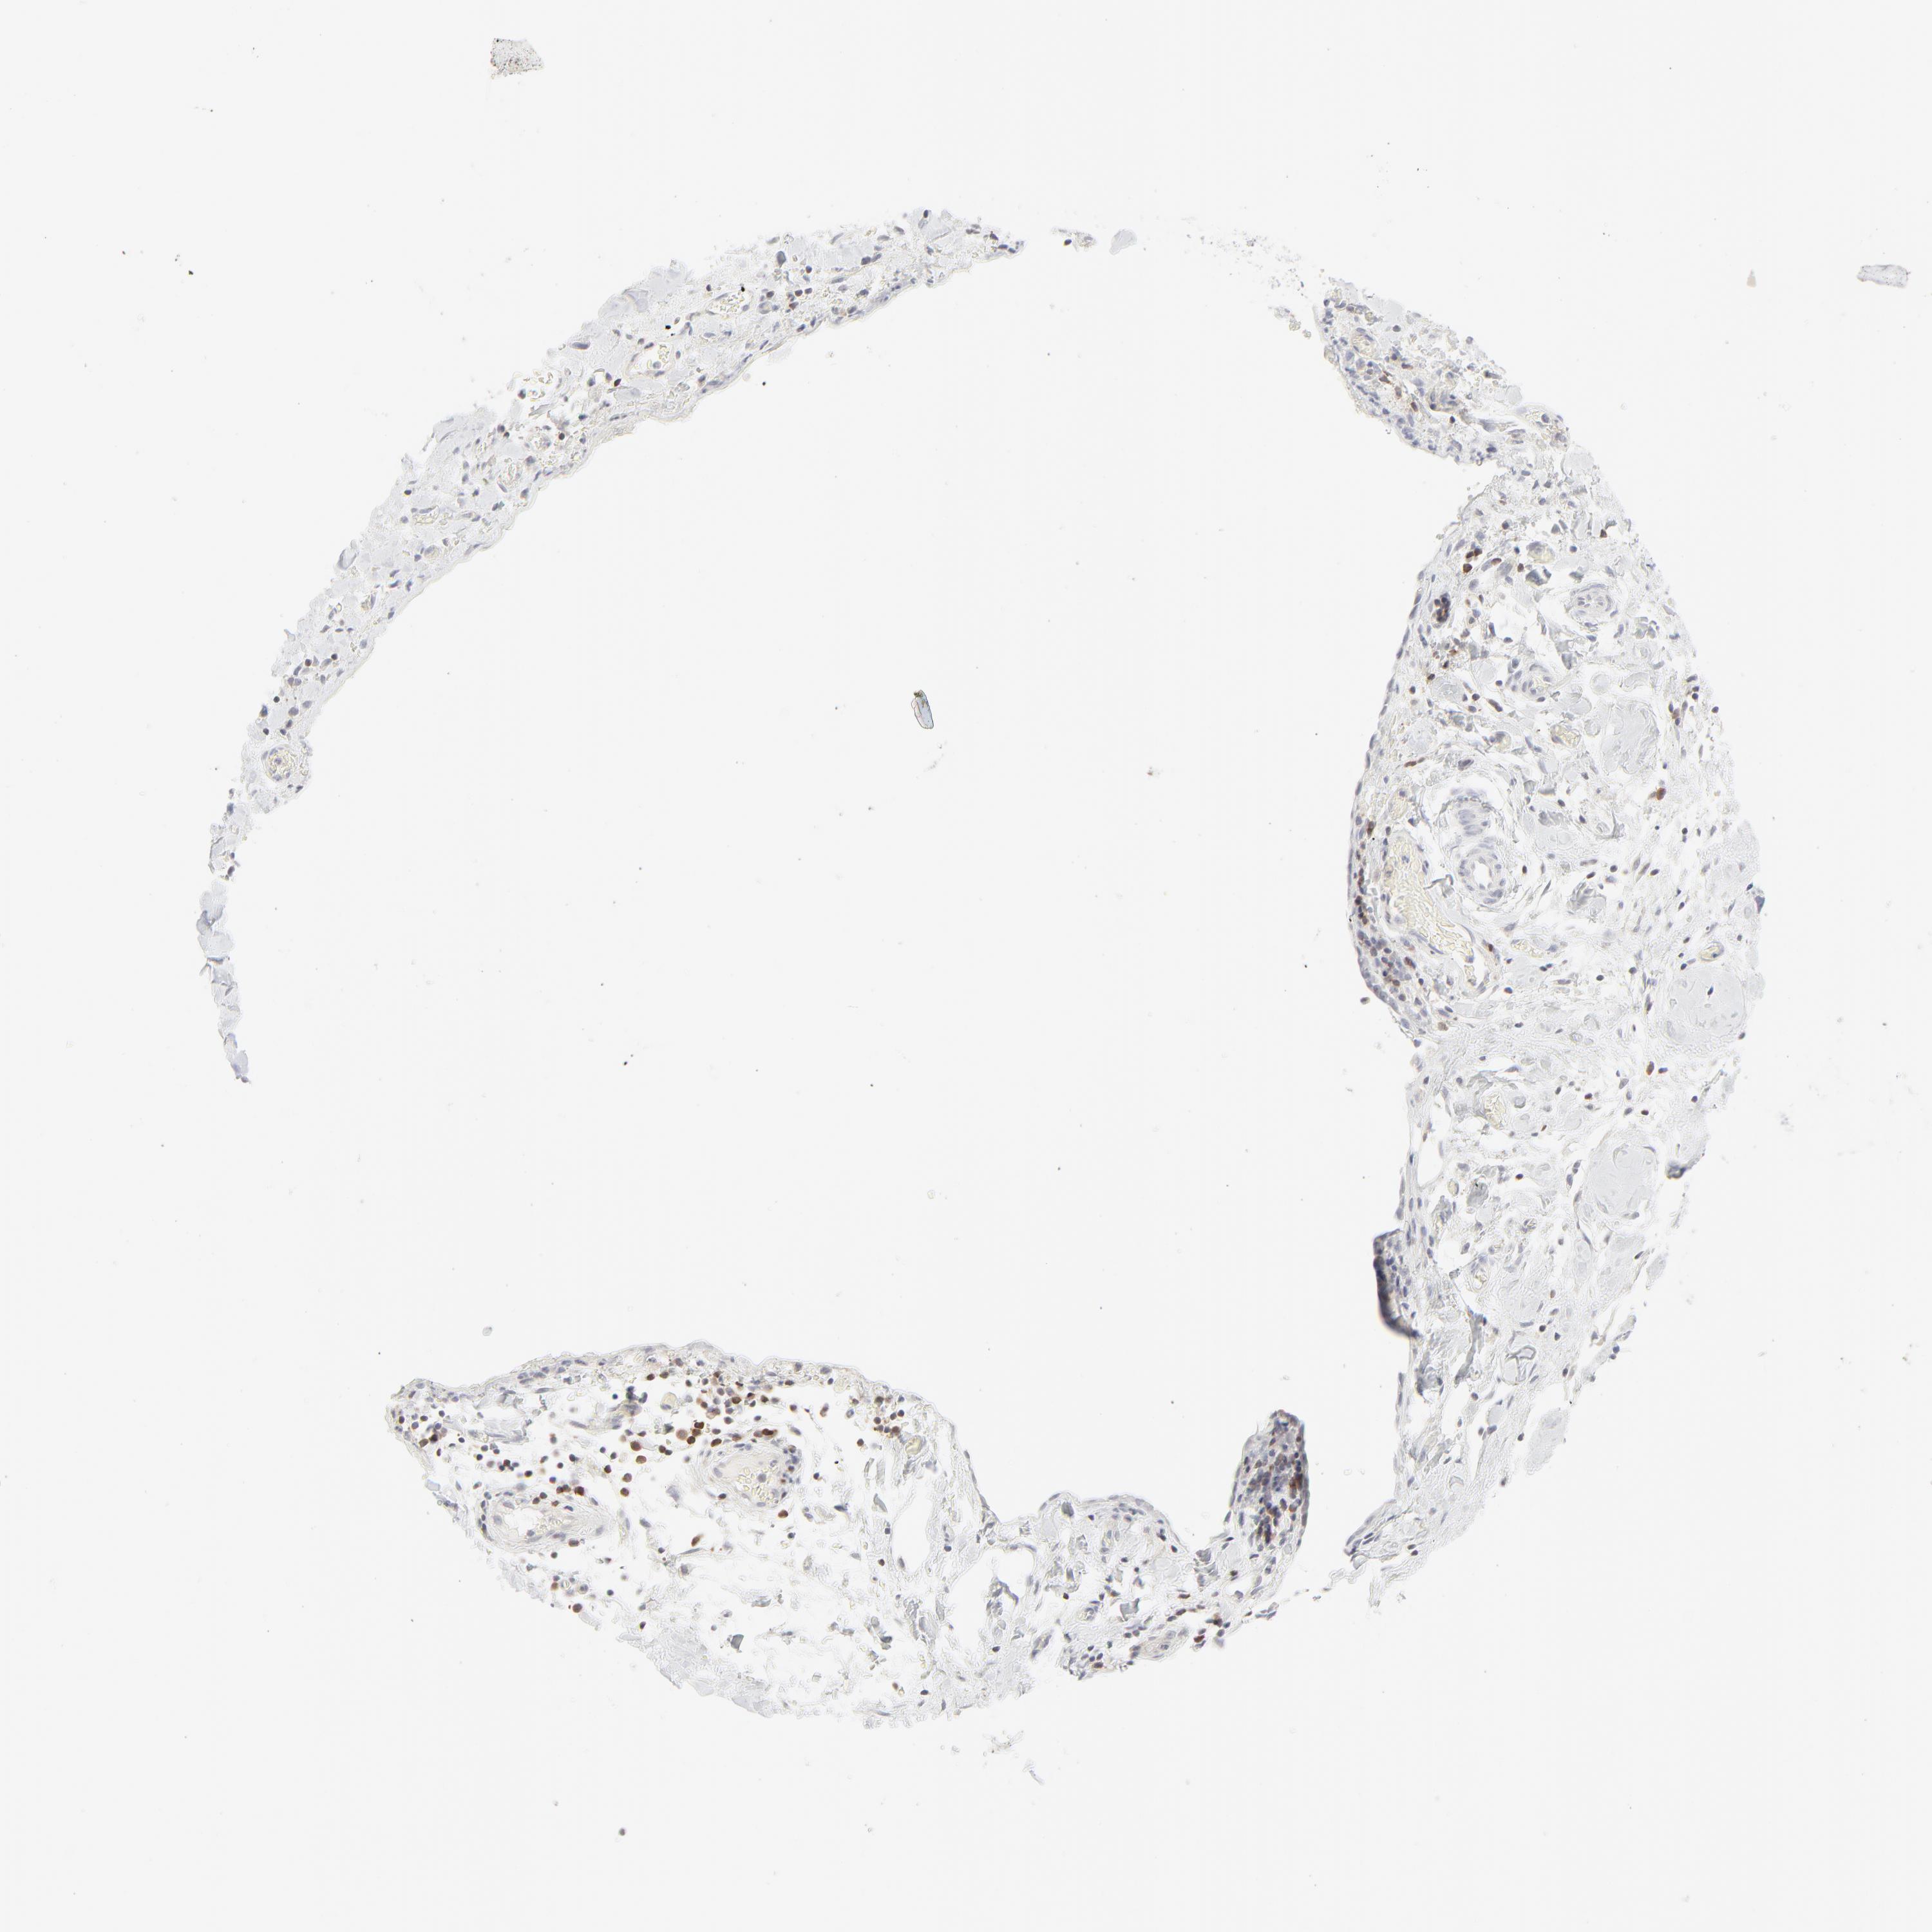

STOMACH CANCER - Protein expressioni

A mouse-over function shows sample information and annotation data. Click on an image to view it in a full screen mode. Samples can be filtered based on level of antibody staining by selecting one or several of the following categories: high, medium, low and not detected. The assay and annotation is described here.

Note that samples used for immunohistochemistry by the Human Protein Atlas do not correspond to samples in the TCGA dataset.

Antibody stainingi

Antibody staining in the annotated cell types in the current human tissue is reported as not detected, low, medium, or high, based on conventional immunohistochemistry profiling in selected tissues. This score is based on the combination of the staining intensity and fraction of stained cells.

Each image is clickable and will lead to virtual microscopy that enables deeper exploration of all samples and also displays staining intensity scores, fraction scores and subcellular localization as well as patient and tissue information for each sample.

Antibody HPA048321

Antibody CAB003843

Staining

High

Medium

Low

Not detected

Intensity

Strong

Moderate

Weak

Negative

Quantity

>75%

75%-25%

<25%

None

Location

Nuclear

Cytoplasmic/membranous

Cytoplasmic/membranous,nuclear

Adenocarcinoma, NOS